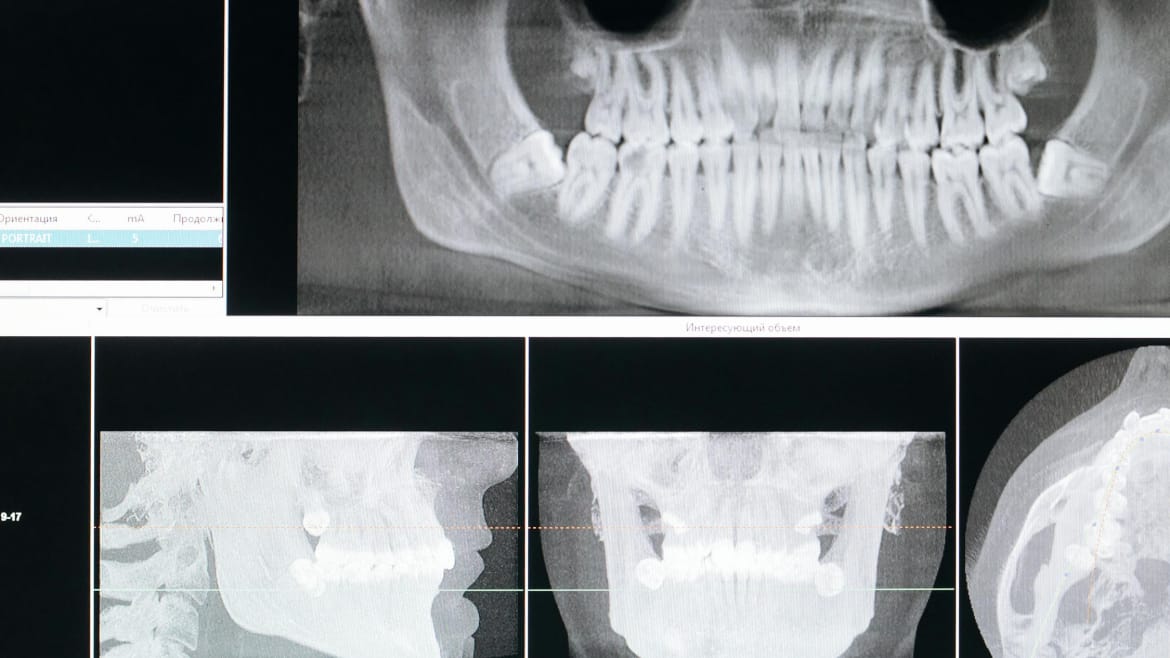

La Miko Dental, echipa de specialiști utilizează tehnici avansate de augmentare osoasă, adaptate fiecărui caz. În plus, consultul pre-implant este realizat cu ajutorul radiografiei 3D, ceea ce permite o planificare precisă și personalizată.